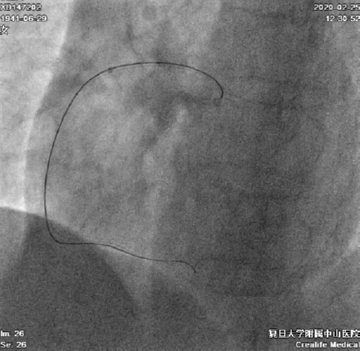

患者右冠异常开口于左冠窦,经左侧桡动脉先后尝试置入7F SAL 0.75SH、1.0SH、EBU 3.5SH、BL 3.25指引导管均无法到达右冠口,最终BL 3.0指引导管成功送至右冠口(图4)

图4